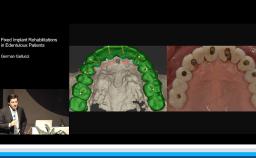

This lecture presents a concept for choosing the type of reconstruction and material for highly esthetic outcomes. Due to the number of restorative possibilities, the selection of an ‘ideal’ material is getting more and more complex. Advantages of all-ceramic materials over traditional metal-ceramics include their tooth-like color and their enamel-like translucency. The main limitation of ceramics is their brittleness, leading to a risk for fracture during clinical service. This lecture discusses the development of modern ceramics with increased stability to reduce this risk, with a focus on high-strength ceramic zirconia and its potential as an alternative to metal. For the processing of zirconia, numerous computer-aided manufacturing procedures are available today. Moreover, multiple clinical studies show promising results for zirconia-based tooth and implant reconstructions.